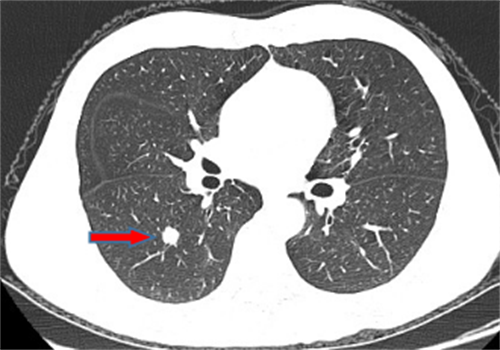

王女士,57岁,体检发现右下肺结节2月,术后病理诊断肺结节为肺隐球菌病。

李先生,45岁,发现右上肺结节2年,近期长大,术后病理诊断肺结节为炎性假瘤。

龙先生,65岁,体检发现右下肺结节,术后病理诊断肺结节为硬化性血管瘤。

郭女士,63岁,体检发现右下肺结节20天,术后病理诊断肺结节为浸润性腺癌。

王女士,65岁,体检发现右上肺磨玻璃结节16天,术后病理诊断肺结节为浸润性腺癌。

王女士,52岁,体检发现右上肺磨玻璃结节7月,术后病理诊断肺结节为原位腺癌。

王女士,35岁,新冠核酸检查阳性7天,胸部CT检查左上肺磨玻璃影,考虑新冠病毒性肺炎。